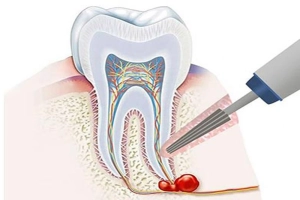

کیست دندان چیست؟

کیست دندان در واقع یک حفره یا کیسهی کوچک است که داخل استخوان فک یا بافت نرم اطراف دندان تشکیل میشود. این کیسه معمولاً حاوی مایع یا بافت نیمهجامد است و در بیشتر موارد، در اثر عفونت یا التهاب مزمن اطراف ریشه دندان ایجاد میشود.

کیست دندان معمولاً بهآرامی رشد میکند و در مراحل اولیه هیچ علامتی ندارد. اما اگر درمان نشود، ممکن است باعث تخریب استخوان فک، حرکت دندانها، درد یا عفونت شود.

- کیست رادیکولار (ریشهای): شایعترین نوع کیست است و معمولاً در اطراف ریشهی دندان عفونی یا مرده ایجاد میشود.

- کیست فولیکولار (کیست دندان نهفته): در اطراف تاج دندانی که هنوز در نیامده (مانند دندان عقل یا نیش نهفته) شکل میگیرد.

- کیست باقیمانده (Residual cyst): زمانی ایجاد میشود که پس از کشیدن دندان عفونی، بخشی از کیست در استخوان باقی مانده باشد.

- کیست پریاپیکال و پارودنتال: این موارد معمولاً در اثر عفونتهای مزمن و مشکلات لثهای به وجود میآیند.

- کیستکتومی (Cystectomy): در این روش، جراح دهان و فک، کل کیست را بهصورت کامل از استخوان خارج میکند. این روش برای کیستهای متوسط تا بزرگ استفاده میشود.

- مارسوپیالیزیشن (Marsupialization): زمانی انجام میشود که کیست خیلی بزرگ باشد و تخلیهی کامل آن ممکن است به فک آسیب بزند. در این روش، بخشی از دیوارهی کیست باز گذاشته میشود تا بهتدریج کوچک شود.

- درمان ریشه (Root Canal Therapy): اگر کیست در اثر عفونت ریشهی دندان ایجاد شده باشد، درمان ریشه قبل از جراحی الزامی است.

- جراحی همزمان با کشیدن دندان: اگر دندان عفونی غیرقابل نگهداری باشد، همزمان با کشیدن، کیست نیز تخلیه میشود.